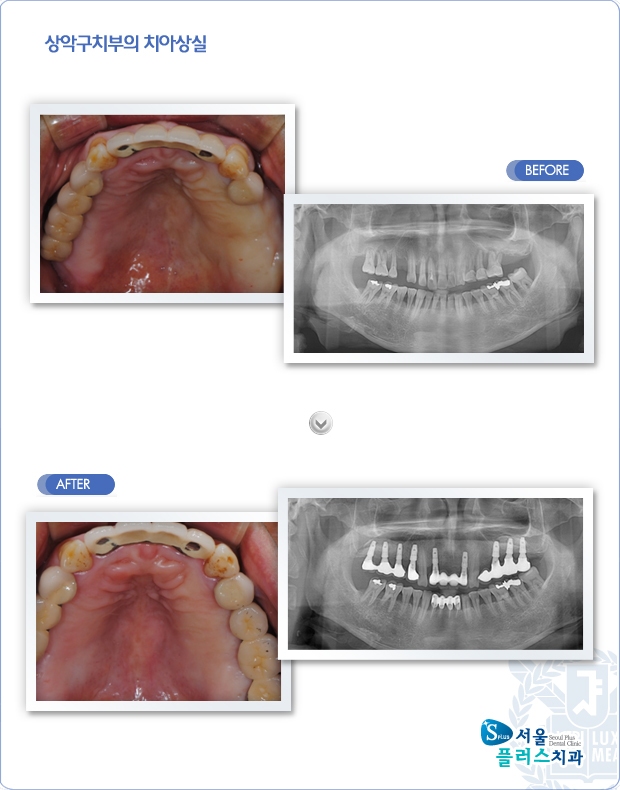

[임플란트] 상악 구치부의 치아상실